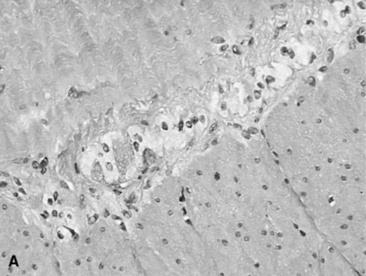

The decision about whether to obtain a biopsy is often based on the ease of obtaining a sample and the relative value of the evaluation that can be made. Very small samples, such as those obtained with an endoscope biopsy instrument, are relatively easy to obtain, but they provide limited information. Full-thickness bowel specimens, obtained by means of ventral midline or flank laparotomy, are more difficult to obtain, but they provide much more information.

Taking a biopsy sample by endoscopy allows the practitioner to choose the biopsy site on the basis of the appearance of the mucosal surface, which most frequently reflects an inflammatory disorder. Conversely, when a biopsy sample is obtained through laparotomy, the serosal surface of the bowel may not reflect a disorder within the bowel wall. In such instances it may be useful to obtain several biopsy specimens. Rectal mucosal biopsies are easily performed. Many instruments can be used to obtain the biopsy specimen, and a uterine biopsy forceps works well. A fold of mucosa can readily be pinched between two fingers, and a sample of this tissue is obtained. The size of the sample is adequate for histologic or bacteriologic examination.